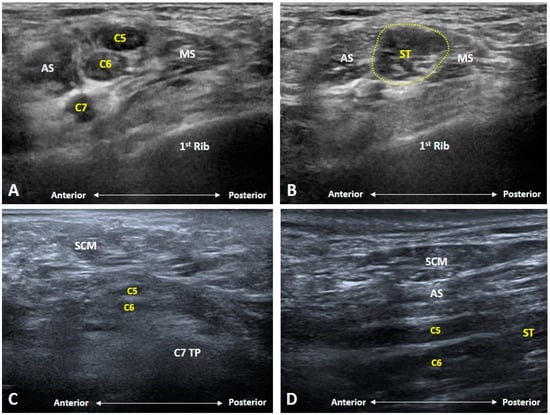

3.2. Is the C7 Transverse Process Easily Recognized?